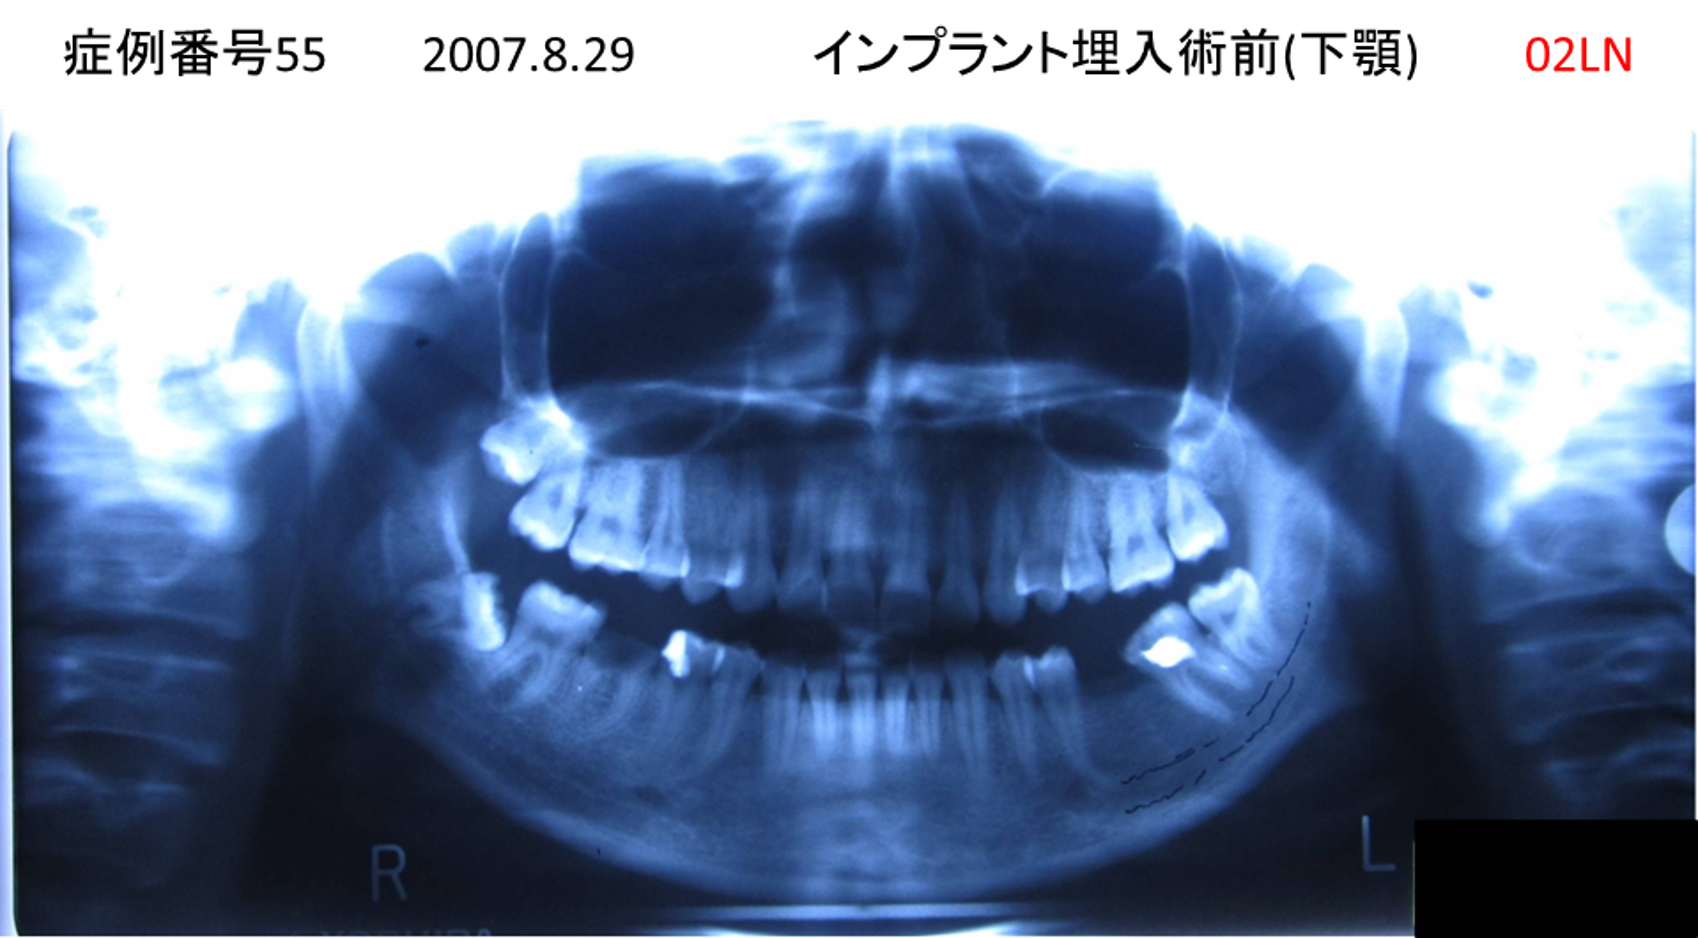

上の前歯が揺れてきた患者様のインプラント症例

| 治療名称 |

インプラント |

| 治療費用 |

390万円+税 |

| 治療期間 |

6か月 |

| 患者さんの症状(主訴) |

上の前歯が揺れてきた。固いものが食べられない。 |

| 治療内容 |

サイナスリフト、抜歯即時インプラント |

| 治療結果 |

上の前歯の揺れが収まった。食べ物がおいしい。 |

| 治療の注意点(リスク/副作用) |

インプラントが壊れたら再治療が必要 |